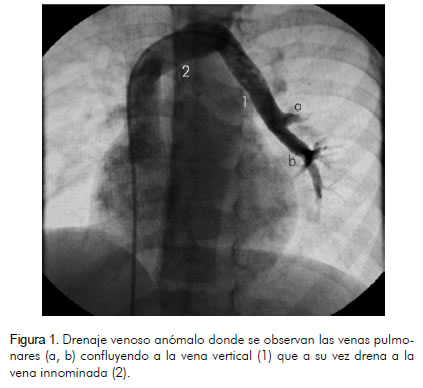

Paciente de 6 años de edad, de género masculino, previamente asintomático, practicante de patinaje, quien tenía controles por cardiopatía congénita en otra institución y fue remitido a la nuestra para valoración especializada y estudios complementarios. El ecocardiograma reportó drenaje venoso anómalo parcial de una vena pulmonar a la vena innominada y estenosis leve de las ramas pulmonares. La radiografía de tórax mostró cardiomegalia a expensas del ventrículo derecho. Se realizó angiografía que reportó conexión venosa anómala pulmonar parcial de dos venas pulmonares a una vena vertical con drenaje de ésta a la vena innominada, sin obstrucciones, Qp/Qs de 2.3:1 y presiones pulmonares normales; se descartó estenosis de las arterias pulmonares (figuras 1 y 2). Fue enviado a cirugía para realizarle toracotomía lateral izquierda (figura 3); se identificaron y disecaron venas pulmonares izquierdas, vena vertical y vena innominada, y se hizo anastomosis termino-terminal del extremo distal de la vena vertical con la orejuela izquierda (figura 4). Ingresó a la unidad de cuidado intensivo donde se vigiló por dos días y posteriormente fue trasladado a piso; luego se le dio de alta en buenas condiciones.